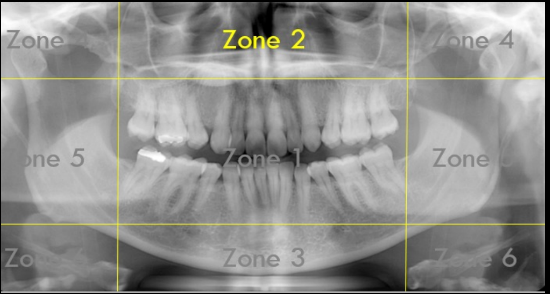

Identify The Zones.

Zone 1: Dentition

Zone 2: Nasal Cavity and Maxillary Sinuses

Zone 3: The Mandible

Zone 4: Temporomandibular Joints (TMJs)

Zone 5: Spine and Ramus

Zone 6: Hyoid Bone

What Zone Is This?

What do we see in Zone 3?